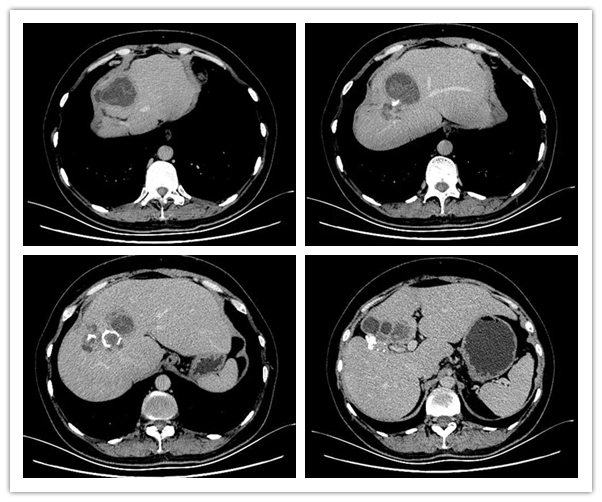

手术前腹部CT

结合患者腹部CT检查,考虑患者为复发性肝囊型包虫病,且有多个包虫病灶,结合化验检查患者有明显肝功能损害,考虑为包虫破入胆道所致,此类病例属疑难复杂性肝囊型包虫病,治疗起来比较棘手,传统手术无法根治性解决,还会导致术后包虫复发、包虫残腔反复感染等并发症出现,为此,科室特邀请中国火箭军总医院段伟宏教授及谢于教授进行了会诊,通过充分的评估及讨论,认为患者可实施肝中叶切除术(肝囊型包虫病根治性切除术),经充分的术前准备后,在段伟宏及谢于教授的帮助下,普外三科在麻醉科及手术室的协作下为患者成功实施了肝中叶切除术(肝多发囊性包虫根治性切除术)、胆总管探查T管引流术,手术过程顺利。